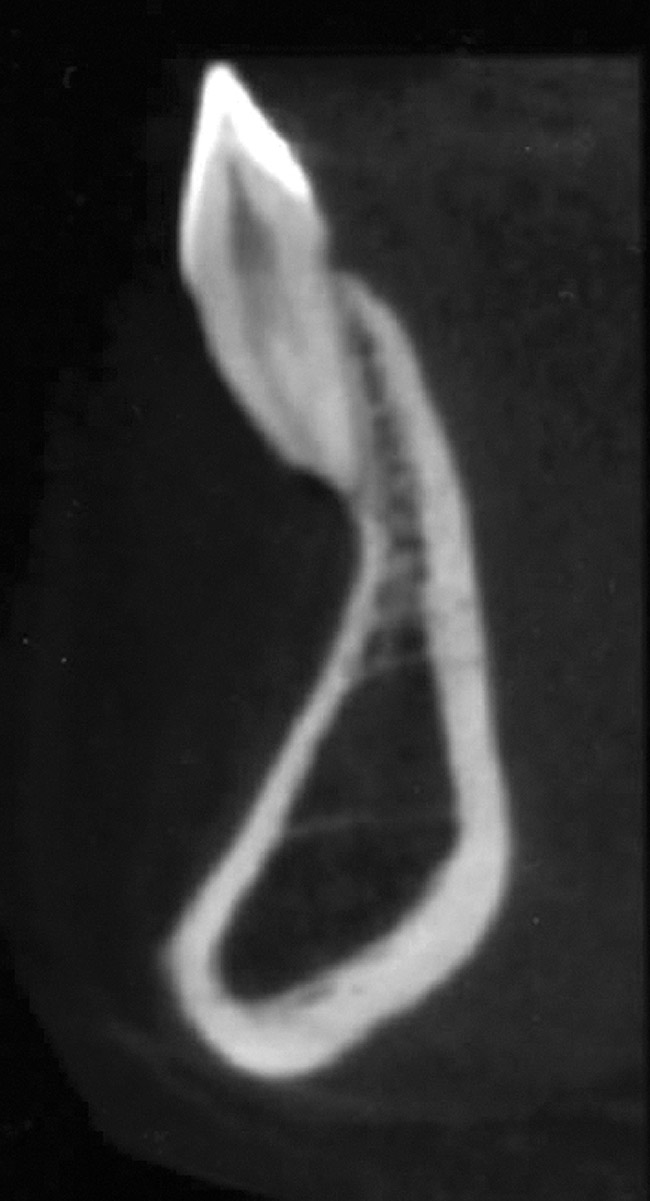

Fig 5. CBCT sagittal view of the same patient showing thin/no bone on the lingual aspect.

Figure 5

When teeth with GR present with an increased labial root inclination and prominence, orthodontic correction of tooth position should be then considered. The decision about whether orthodontic treatment is possible depends on the thickness of the bone lingual to the affected root. The only modality to accurately assess the labio-lingual thickness of the alveolar bone is cone-beam computerized tomography (CBCT) imaging. Studies that compared measurements on cadavers and CBCT showed that CBCT measurements are an accurate representation of the clinical bone thickness.31-33

The lingual bone thickness of mandibular permanent teeth in a sample of adolescent and young adults before orthodontic treatment has been reported.34 The measurements were performed on axial sections of CBCT, 4 mm and 8 mm apical to the CEJ. The average lingual bone thickness was 0.79 mm and 1.02 mm for central and lateral incisors, respectively, at 4 mm distance from CEJ. At 8 mm apical to the CEJ, the width increased to 1.81 mm and 1.75 mm for central and lateral incisors, respectively.34 Another study on cadavers reported an average thickness of 2.5 mm and 2.6 mm for central and lateral incisors, respectively, at 6 mm from the alveolar crest, meaning approximately 8 mm distance from the CEJ.35

Based on these data, a minimum of 2.5 mm of lingual alveolar bone thickness, measured on CBCT views at 8 mm apical to the CEJ, is recommended for orthodontic tooth repositioning of a labially displaced root.

In cases with thin lingual bone, as measured on CBCT (<2.5 mm at a level of 8 mm apical to the CEJ), orthodontic treatment is not advisable, leaving surgical root coverage as the only option. However, the prognosis for this procedure is poorer, because the predominant cause is not addressed. Figure 4 shows the frontal clinical view of a patient with a hyperdivergent growth pattern who presented with post-orthodontic GR of a labially displaced lower central incisor. The sagittal CBCT view (Figure 5) shows complete absence of lingual bone, which contraindicated orthodontic tooth repositioning.